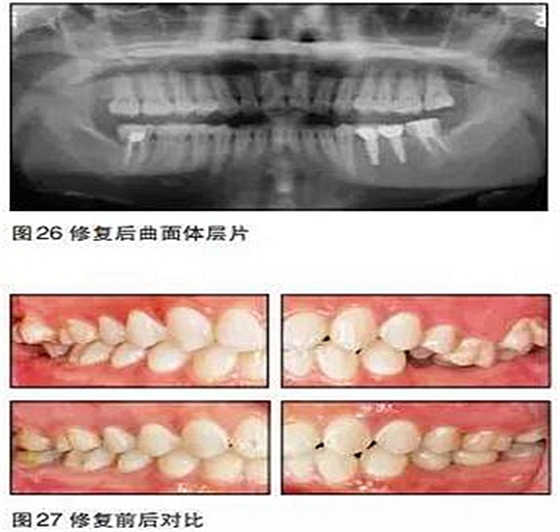

在本病例中,患者的主觀愿望是想通過種植來修復(fù)缺失牙??趦?nèi)檢查及口腔曲面體層片顯示患者缺牙區(qū)的骨質(zhì)良好,骨量充分,但咬合情況非常復(fù)雜。如果不先通過正畸治療來改善咬合而直接進(jìn)行種植手術(shù),那么后期的修復(fù)將異常困難。

本病例的難點(diǎn)在于如何創(chuàng)造適合種植的咬合條件。17、47、27、37正鎖,25、26過長。傳統(tǒng)矯治正鎖時(shí)往往采用上下頜交互牽引的方式,但這種方法會導(dǎo)致磨牙不必要的伸長,且有明顯的疼痛感。本病例采用種植支抗釘技術(shù),在矯正17、47、27、37

正鎖的同時(shí)壓低相應(yīng)牙齒,在較短的時(shí)間內(nèi)完成了后牙鎖及伸長牙的矯正,且患者感覺較為舒適。

35、36種植時(shí)采用骨水平的NobelActive植體;由于植體位置比較理想,修復(fù)體采用螺絲固位的氧化鋯基臺一體冠,便于今后牙冠及種植體的維護(hù)。最終種植修復(fù)完成后在咬合、美觀、牙齦乳頭充盈等方面都取得了滿意的效果。